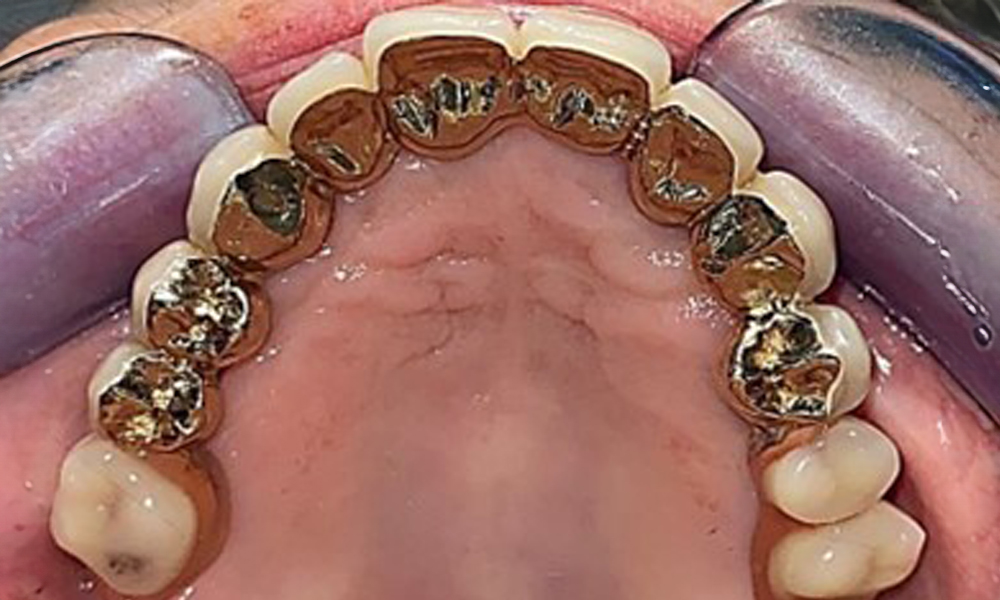

Occlusal view: Maxilla with tooth and implant-supported telescopic prostheses.

Fig. 2: Occlusal view: Maxilla with tooth and implant-supported telescopic prostheses